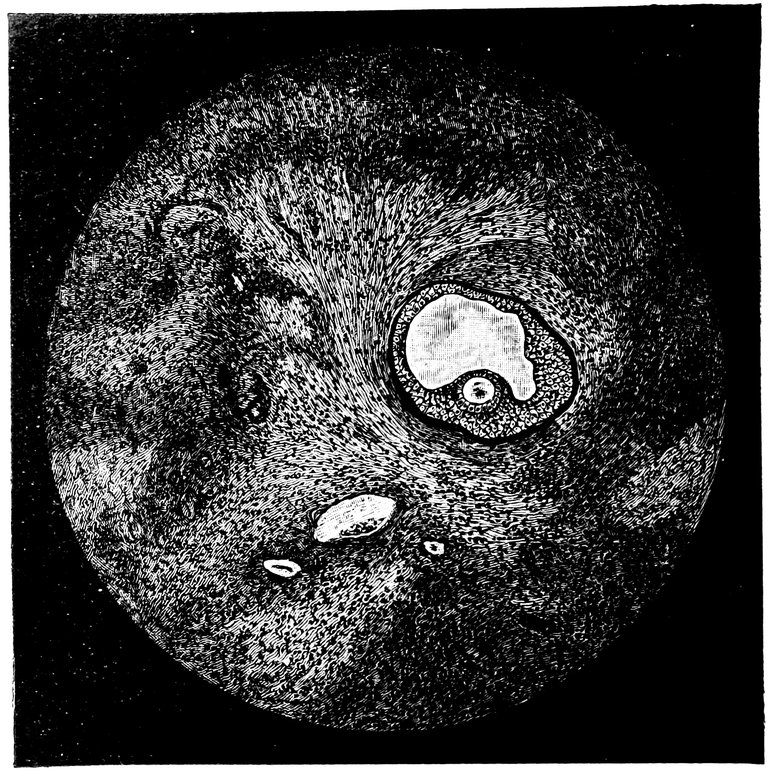

| 15. | Primitive follicles | 58 |

| 16. | Ripening follicles | 61 |

| 17. | Graafian follicles | 62 |